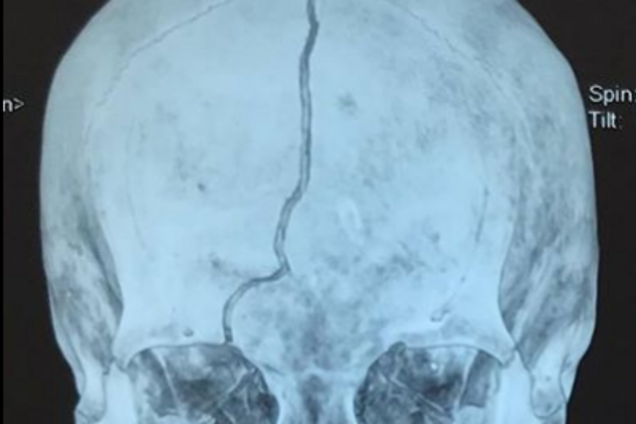

Бабушка сейчас в реанимации, она находится в коме после тяжелейшей черепно-мозговой травмы. Шансов на то, что выживет, очень мало.